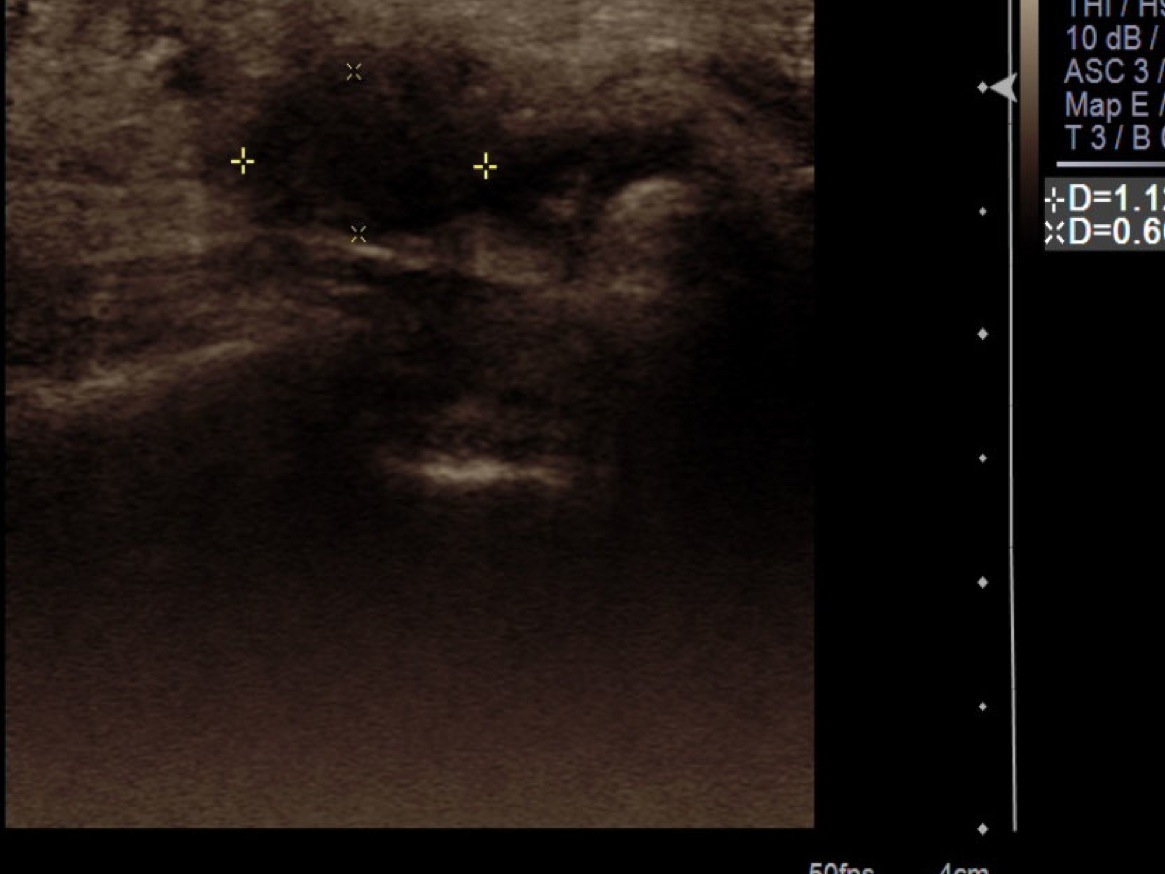

8. Once numb, under ultrasound guidance, advance needle into the neuroma.

9.Test inject with 1% lidocaine. If flow easily exchange for 3cc syringe with injectable steroid (kenalog 40mg/cc) and ropivacaine. Inject approximately 3/4cc into neuroma.